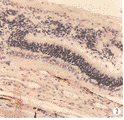

2.2 组织学检查结果:移植前胚胎期2周供体视网膜,仅见单一多细胞层,富含细胞核,尚未见内外颗粒层的分化。移植术后1周移植区受体视网膜神经上皮与色素上皮分离,被移入的视网膜细胞失去原来正常的片段状排列,大部分呈花环状排列,花环由中央空腔及周围向心排列的细胞团组成,近中央处细胞核轻度椭圆状,深染,花环边周核圆,淡染(图1)。移植后2~3周:移植区可见两种细胞的继续分化分层,近中央区胞浆红染,形态类似外节,指向中央空腔,但较短。个别地方未形成花环,呈条形排列,可见内外核层分化,相当外节部分指向受体色素上皮层,也有朝向受体内界膜方向(图2)。4周移植物细胞排列仍大部分呈花环状,内外核层分化明显,在受体及植片之间可见核固缩细胞。实验组和对照组术后1~4周未见明显脉络膜血管扩张、充血,无淋巴细胞及单核巨噬细胞浸润。

图1 花结样生长

Fig.1 Rosette growing